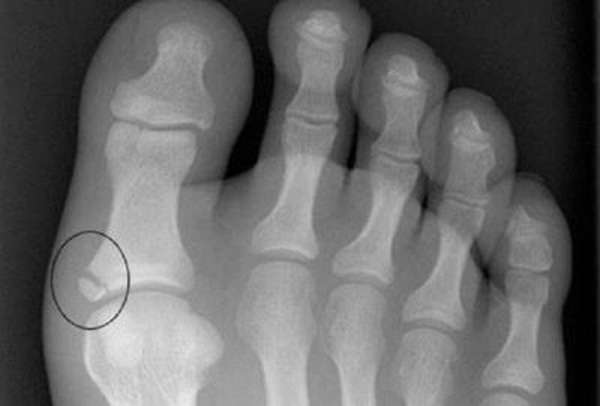

Важное значение в диагностировании переломов большого пальца ноги отдается рентгенографии ступни в одной — двух проекциях. Благодаря данному параклиническому исследованию с точностью до 95-99 % можно распознать, имеется ли травма пальца ноги, определяя с точностью до миллиметра место перелома и местоположение костных отломков.

Далее пациента направляют на рентген для получения снимка. Рентгенография необходима в нескольких проекциях. На основании снимков и предварительного обследования пациента врач делает окончательные выводы относительно характера и степени тяжести травмы.

Делать рентген придется и в дальнейшем – для контроля динамики в процессе лечения. Важно следовать рекомендациям врача и не прерывать заботу о сломанном пальце, как только внешние признаки и болевые ощущения станут менее заметными.

Недолеченные переломы, закрытые и открытые, ведут к серьезным последствиям для здоровья. Финальный рентгеновский снимок продемонстрирует полное срастание костей. На этом этапе диагностика и лечение считаются завершенными.